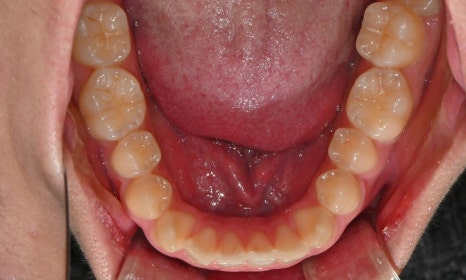

2024.12. 초진 구내사진 - 연세정원치과

정밀 검진 결과, 하악 치열이 좌측으로 틀어져 있었고 그로 인해 위아래 치아 중심선이 일치하지 않았습니다. 아래 치열이 전체적으로 전방 위치하여 아래 입술 돌출이 더 도드라져 보이는 상태였습니다. 그리고 상악궁이 하악궁보다 좁아서 앞니 부위 일부 반대로 물리는 치아 교합도 관찰되었습니다. 특히 외상 치아의 경우, 교정력 적용시 추가적인 염증성 치근 흡수 위험이 존재하기 때문에, 치료 중 지속적인 관찰이 필수적인 상황이었습니다.